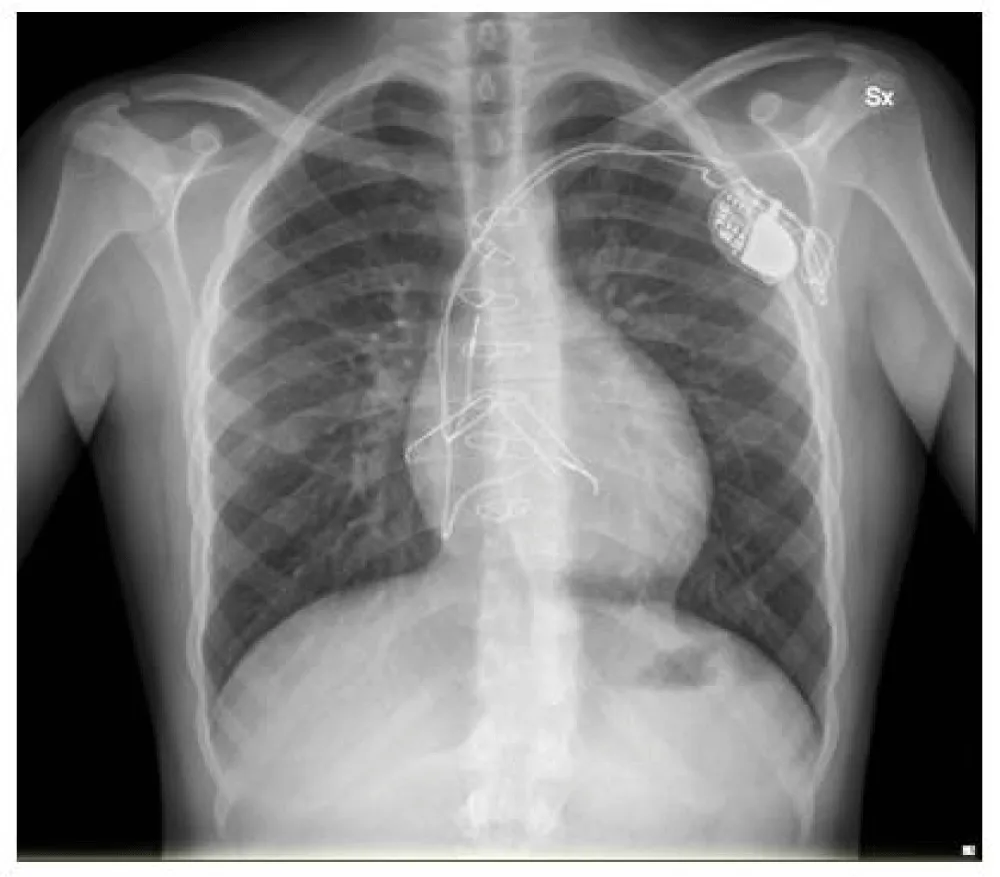

Three years later, the patient developed a subxiphoid abscess involving the abandoned epicardial leads, with adjacent lung involvement. Echocardiography also revealed a fragment of the lumenless lead, retained for four years and initially adherent to the free wall of the subpulmonary left ventricle, now oscillating clockwise within the ventricular cavity (Videos 1,2). Radiological imaging confirmed an additional fracture of the previously abandoned lead fragment (Figure 1).

The standard extraction technique involved engaging the fragment with the snare, advancing an appropriately sized introducer over the snare under steady traction, and, once the fragment was fully enclosed within the introducer, applying additional traction to achieve complete retrieval. Ultimately, a 15-mm Lasso Snare was used to capture the remaining lead segment adherent to the subpulmonary free wall of the left ventricle. (video 3) With gentle, continuous traction, the fragment was advanced into the introducer and removed in a single piece. The procedure was completed uneventfully (Figure 2).